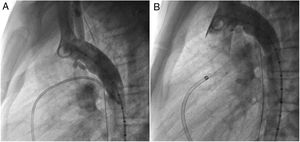

MethodsAll consecutive pediatric patients referred to our center for percutaneous PDA closure from January 2006 until September 2018 were included in this study. Medical record data was collected and reviewed retrospectively. Informed written consent was obtained from the parents or legal guardians. Indications for closure were presence of cardiac murmur, left-sided volume overload detected by non-invasive cardiac imaging, or signs of heart failure. All procedures were performed under general anesthesia. Arterial access was obtained in all patients. An intravenous bolus injection of 100 IU/kg heparin was administered at the start of the procedure. Our endocarditis prophylaxis protocol consisted of cephazolin 25-30 mg/kg every eight hours for 24 hours, and no anti-aggregation was advocated. In every patient, an aortogram was performed in the lateral projection to define the morphology and size of the duct. According to these results, feasibility for percutaneous closure was determined and, when deemed feasible, appropriate devices were selected. At our department, the Nit-Occlud® occlusion device (pfm, Cologne, Germany) has been available since 2006, with the Amplatzer™ duct occluder being implemented in 2011. As standard of care, all devices were preferably deployed anterogradely. A post-implantation aortogram was obtained to check for residual shunts or any anomaly in the device position. All patients were assessed six hours after the procedure for hemodynamic instability and unpalpable distal arterial pulses. The following day, before discharge, the location of the device was noted on a chest radiograph and a transthoracic echocardiography was performed to exclude residual leakage or other complications. Clinical and echocardiographic follow-up assessments were performed at one, three, six and twelve months after the procedure, and annually thereafter.

A coil was used in 139 patients (62.9%) and an Amplatzer duct occluder was used in 79 patients (35.7%). In the three remaining patients (1.4%), an Amplatzer vascular plug was used for closure (Figures 2-8). Despite the higher overall rate of coil device implantation, Amplatzer duct occluder usage had been clearly superior since 2011. Of all coil devices used, 55% were either 4x4 mm or 5x4 mm in size (Figure 9), and of all duct occluder devices used, 72% were Amplatzer duct occluder I 6x4 mm or 8x6 mm in size (Figure 10), which correlates to the fact that most patients who were referred had small- to moderate-sized ductus arteriosus. While ADO II and ADO II AS devices can be implanted in a retrograde fashion, only on two occasions was a retrograde deployment performed (both ADO II devices).

Effective ductal closure was achieved in every treated patient, as confirmed by a post-implantation aortogram, with three patients (1.4%) presenting residual shunting. In these patients, the shunting was considered to be trivial, no second cardiac catheterization was ever attempted, and there was no described hemolysis. The residual shunting had no significant relationship to the size or shape of the ductus, while being more frequent in patients who were treated with coils.